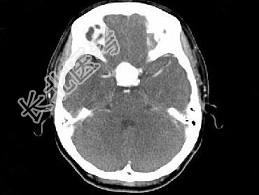

- 单项选择题女,43岁, 反复头痛10个月,CT检查如图, 最可能的诊断是 ( )